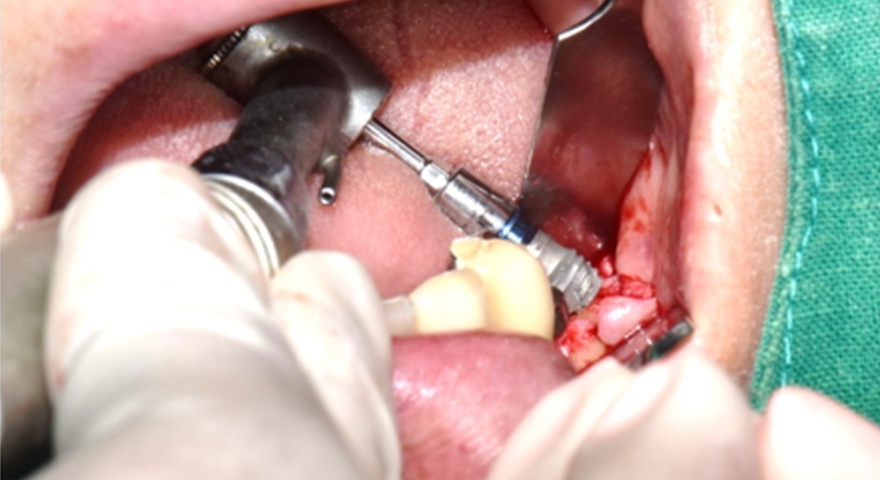

Після проведення стандартної імплантації в ділянках з оголеною різьбою було застосовано техніку DUK: на імплантат наносили спочатку пастоподібний матеріал, далі — гранули, після чого укладали мембрану та закривали клапті швами без натягу. Всі пацієнти отримували антибіотики (амоксицилін) та знеболення (ібупрофен), а через шість місяців — проходили контроль та біопсію ділянки.

Клінічно спостерігалося повне загоєння без ускладнень. Не було зафіксовано випадків десісценції, інфекцій чи оголення мембран. Всім пацієнтам були встановлені постійні ортопедичні конструкції на імплантатах.

Рис. 2. (A) Пацієнт із виявленою необмеженою (non-contained) втратою кісткової тканини та оголенням імплантату з букального боку на момент встановлення імплантату. (B) Нанесення основного шару пастоподібного кісткового матеріалу перед внесенням гранульованого кісткового трансплантата. (C) Укладання колагенової мембрани з покриттям зони трансплантації — від букального до піднебінного боку — та фіксували за допомогою внутрішніх періостальних швів. (D) Через шість місяців після аугментації — візуалізується регенерація кістки з букального боку в ділянці раніше оголеної різьби імплантату.